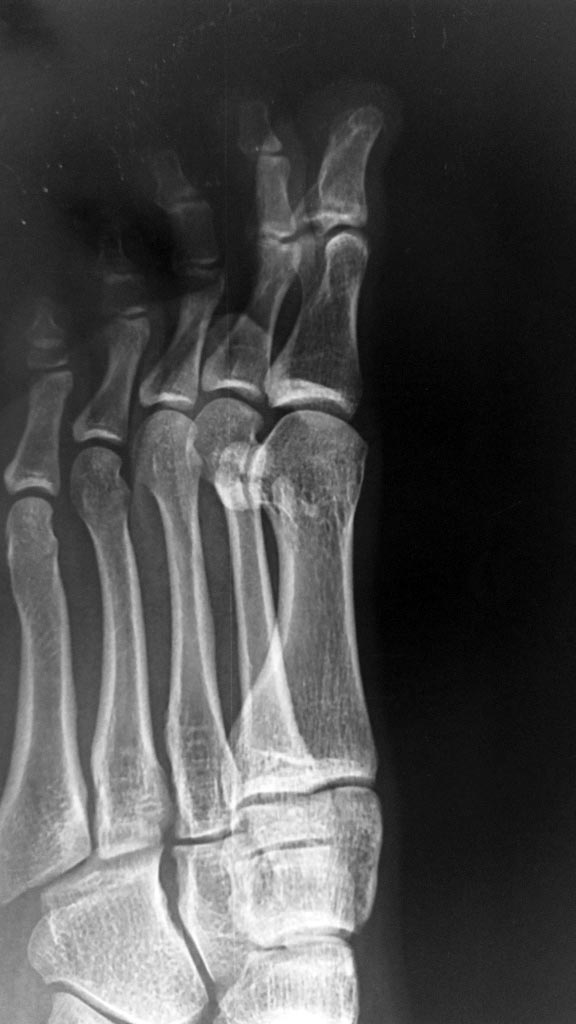

Снимки забыл приложить, извиняюсь.

По снимкам сложно определить, свежий ли это перелом или состоящая из двух частей сесамовидная кость. Поэтому смысл в МРТ есть. Еще на переднезадней рентгенограмме видны преобладание длины первой плюсневой кости и достаточно очевидные уже признаки артроза первого плюснефалангового сустава. Есть ли ограничение подвижности ПФС1 (hallux limitus)?